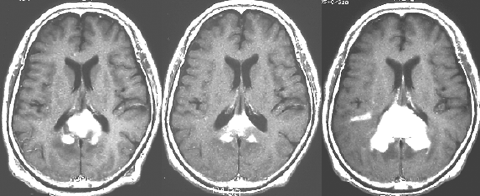

これは1990年代の古い例ですがリンパ腫の増大が早いことをお見せします。左側のはTHP-COPという化学療法をする前のものです。真ん中のは化学療法から4日目で,腫瘍は小さくなりました。でも,2コース目の化学療法の直前(4週間後)にもう一度MRIをしてみたらすごく大きくなっていました。この化学療法は効いているのだか効いていないのだか判らないことになります。化学療法を行なうならとても強い薬剤を使わなければなりませんし急がなければなりません。